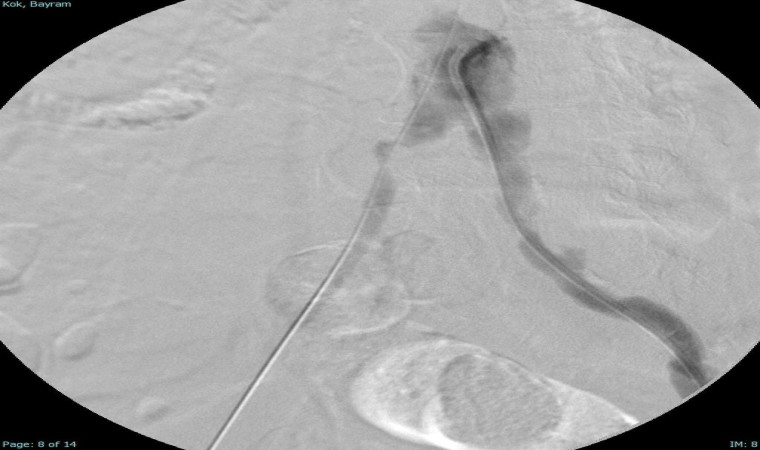

Türkiye’nin ilk yerli stent grefti Bezmiâlem Vakıf Üniversitesi Tıp Fakültesi’nde Prof. Dr. Cengiz Köksal ve Doç. Dr. Emre Selçuk’un öncülüğünde Artven koordinasyonuyla bir hastaya başarıyla uygulandı. Doç. Dr. Emre Selçuk, bu büyük adımı şöyle değerlendirdi:

"Stent-greft teknolojisi, damar tedavilerinde kritik bir rol oynuyor. Damar balonlaşması veya yaralanma riski olan hastalarda bu teknolojinin önemi daha da artıyor. Artık bu teknolojiyi Türkiye’de üretiyor olmamız, operasyon başarımızı artırmanın yanı sıra, hasta güvenliğini de üst seviyelere taşıyacaktır. Türkiye’nin tıbbi alandaki bu başarısında yer almaktan büyük gurur duyuyoruz. Atlas Stent Greft, Türk mühendisliğinin ve Türk doktorlarının inovasyonunun ne kadar ileri seviyede olduğunun bir göstergesidir."